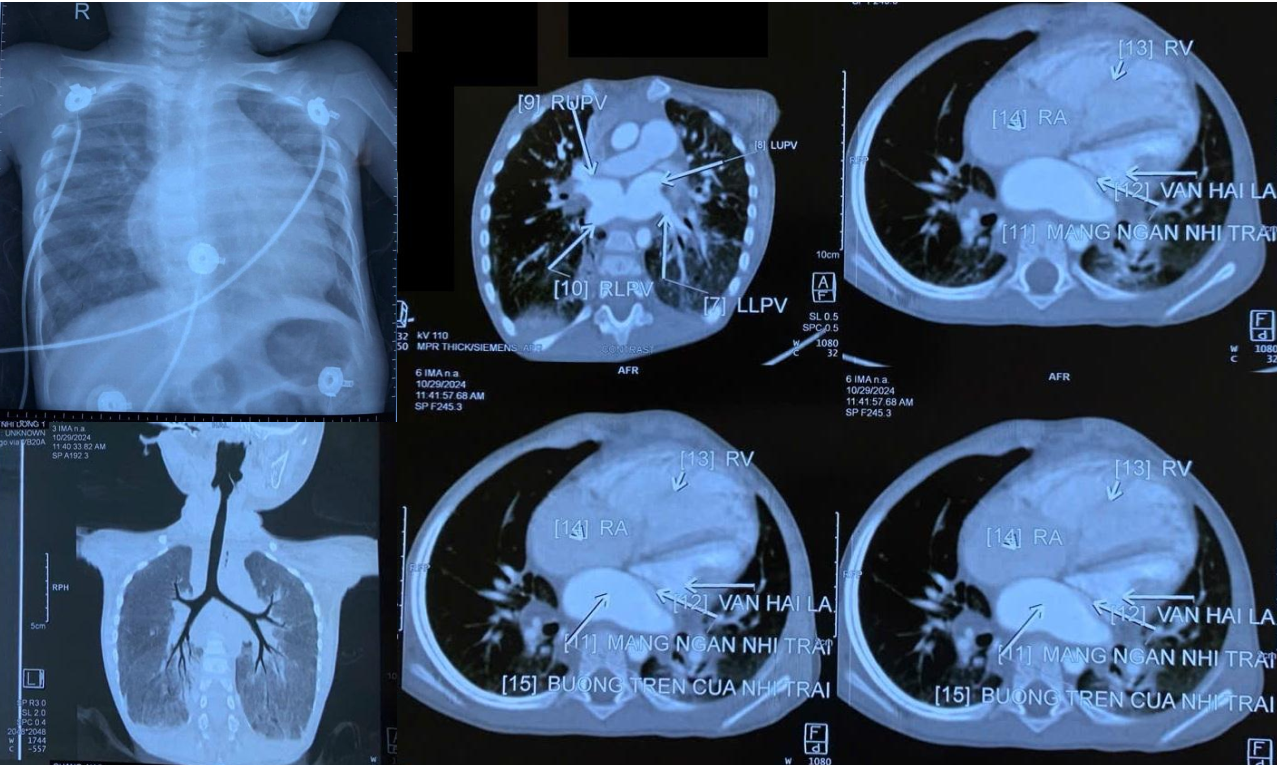

Khoảng 5 ngày trước khi nhập viện, bệnh nhi có biểu hiện thở mệt tăng dần đe dọa tính mạng. Gia đình vội chuyển bé sang Bệnh viện Nhi Đồng 1 (TPHCM). Qua các kết quả thăm khám, kiểm tra hình ảnh và thực hiện các xét nghiệm, các bác sĩ đã loại trừ khả năng trẻ mắc bệnh lao phổi và chẩn đoán trẻ bị bệnh tim có màng ngăn nhĩ trái.

BS-CKII Nguyễn Trí Hào, Trưởng khoa Tim mạch, Bệnh viện Nhi Đồng 1 cho biết: “Đây là ca bệnh hiếm gặp (tỷ lệ khoảng 1/1.000 trong số bệnh nhân tim bẩm sinh). Mỗi năm tại Nhi Đồng 1 chỉ tiếp nhận khoảng 1 đến 2 ca tương tự trường hợp trên. Bệnh lý trên khiến máu bị ứ lại trên phổi. Nếu chưa từng gặp bệnh lý này, bác sĩ rất dễ chẩn đoán nhầm sang bệnh lao phổi”.

Khi trẻ nhập viện, tình trạng bệnh đã diễn tiến nặng, bóng tim to, tim phải giãn lớn, sức co bóp của tim giảm sâu, áp lực động mạch phổi rất cao. Để tránh nguy cơ tử vong cho bệnh nhi, các bác sĩ đã hội chẩn và chỉ định thực hiện cuộc phẫu thuật cắt màng ngăn nhĩ trái.